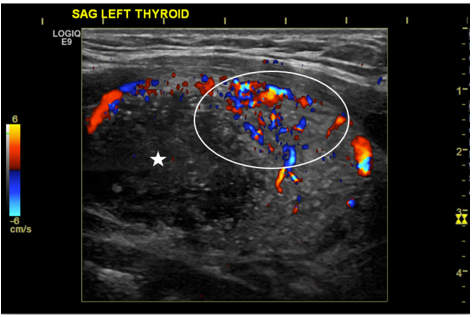

Papillary thyroid cancer has the fastest increasing incidence of any thyroid malignancy and accounts for the majority of thyroid neoplasms (75-85%). It is also the most common type of thyroid cancer to develop from radiation exposure1. Papillary thyroid cancer typically occurs in caucasions and has a female predilection (3:1 ratio), with a peak age of incidence between 25-50 years-old. It commonly presents as a painless neck mass. While no specific laboratory tests exist for diagnosis, elevation in thyroxine, triiodothyronine, or TSH can be seen. Radiology plays a crucial role in the diagnosis of papillary thyroid cancer, with ultrasound being one of the initial steps in the workup. Radioiodine (I-131) nuclear medicine studies can be used to check for distant metastases and ablate thyroid cancer. Thyroid lobectomy is the main treatment, with total thyroidectomy being reserved for higher risk tumors. We report an unusual clinical presentation of the diffuse sclerosing variant of papillary thyroid cancer in a 16-year-old male, who presented with a painless neck mass that had been growing over the past year. The patient subsequently received a total thyroidectomy and radioiodine treatment.References

Kim HS, Han B-K, Shin JH, et al. Papillary thyroid carcinoma of a diffuse sclerosing variant: ultrasonographic monitoring from a normal thyroid gland to mass formation. Korean J Radiol. 2010;11(5):579-582.